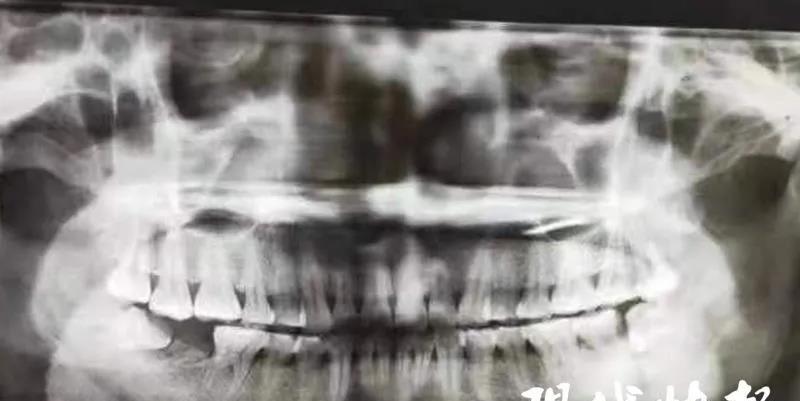

智齿,意思就是牙槽骨上方,最后面的第三颗磨牙,通常情况下位于牙弓的最后方。每个人智齿的数量都不太一样,1-4颗都是有可能的。[1]

这么说你可能比较难理解,直白点就是你现在从正中间的门牙开始往里面数,数到第八颗,那个就是智齿!